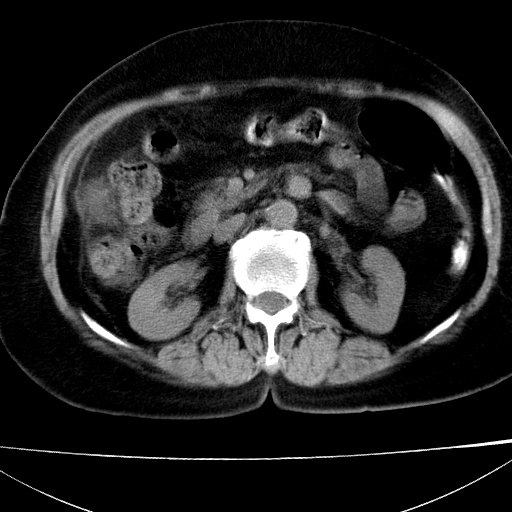

患者女74岁;右上腹胀痛1月,伴恶心,无发热;生活在疫水区。有术后病理及术后半年的追踪ct.

1)慢性血吸虫病(典型)。2)肝硬化。3)肝癌?4)胆囊炎。5)少量腹水。6)右侧少量胸腔积液。

支持.边缘见高密度线条样钙化影.

肝脏体积缩小,肝裂增宽,边缘不平呈波浪状,肝右叶见分隔状条索形钙化,亦见多结节低密度灶,边界不清,肝周可见少许液性暗区,胆囊增大内密度均匀,脾脏下缘低于脏脏的下缘,胸腔亦见液性暗区,余未见明显异常.

诊断:1肝硬化并慢性吸血虫病,脾肿大

2肝内占位,考虑肝癌可能性大,建议做增强

3胆囊炎, 4少量腹水及胸水

胆囊增大饱满,壁增厚。胆囊颈部见软组织密度影。临近肝右叶前段见片状低密度区,病灶下部见条状钙化,少量胸腹腔积液。意见:胆囊颈癌累及肝脏。

病人以胆囊癌手术的,病理结果为中分化腺癌。

现在看看肝右叶内圆形低密度影你们考虑什么呢?

肝内圆形低密度影考虑扩张的胆管

请看3mm重建像如下: